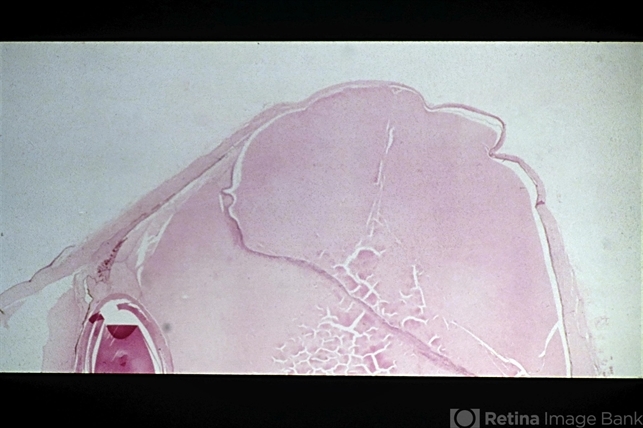

- sequelae, sclera, staphyloma

- Sequelae. Increased intraocular pressure has resulted in stretching and thinning of the sclera in the equatorial region, resulting in an equatorial staphyloma (H&E x3).